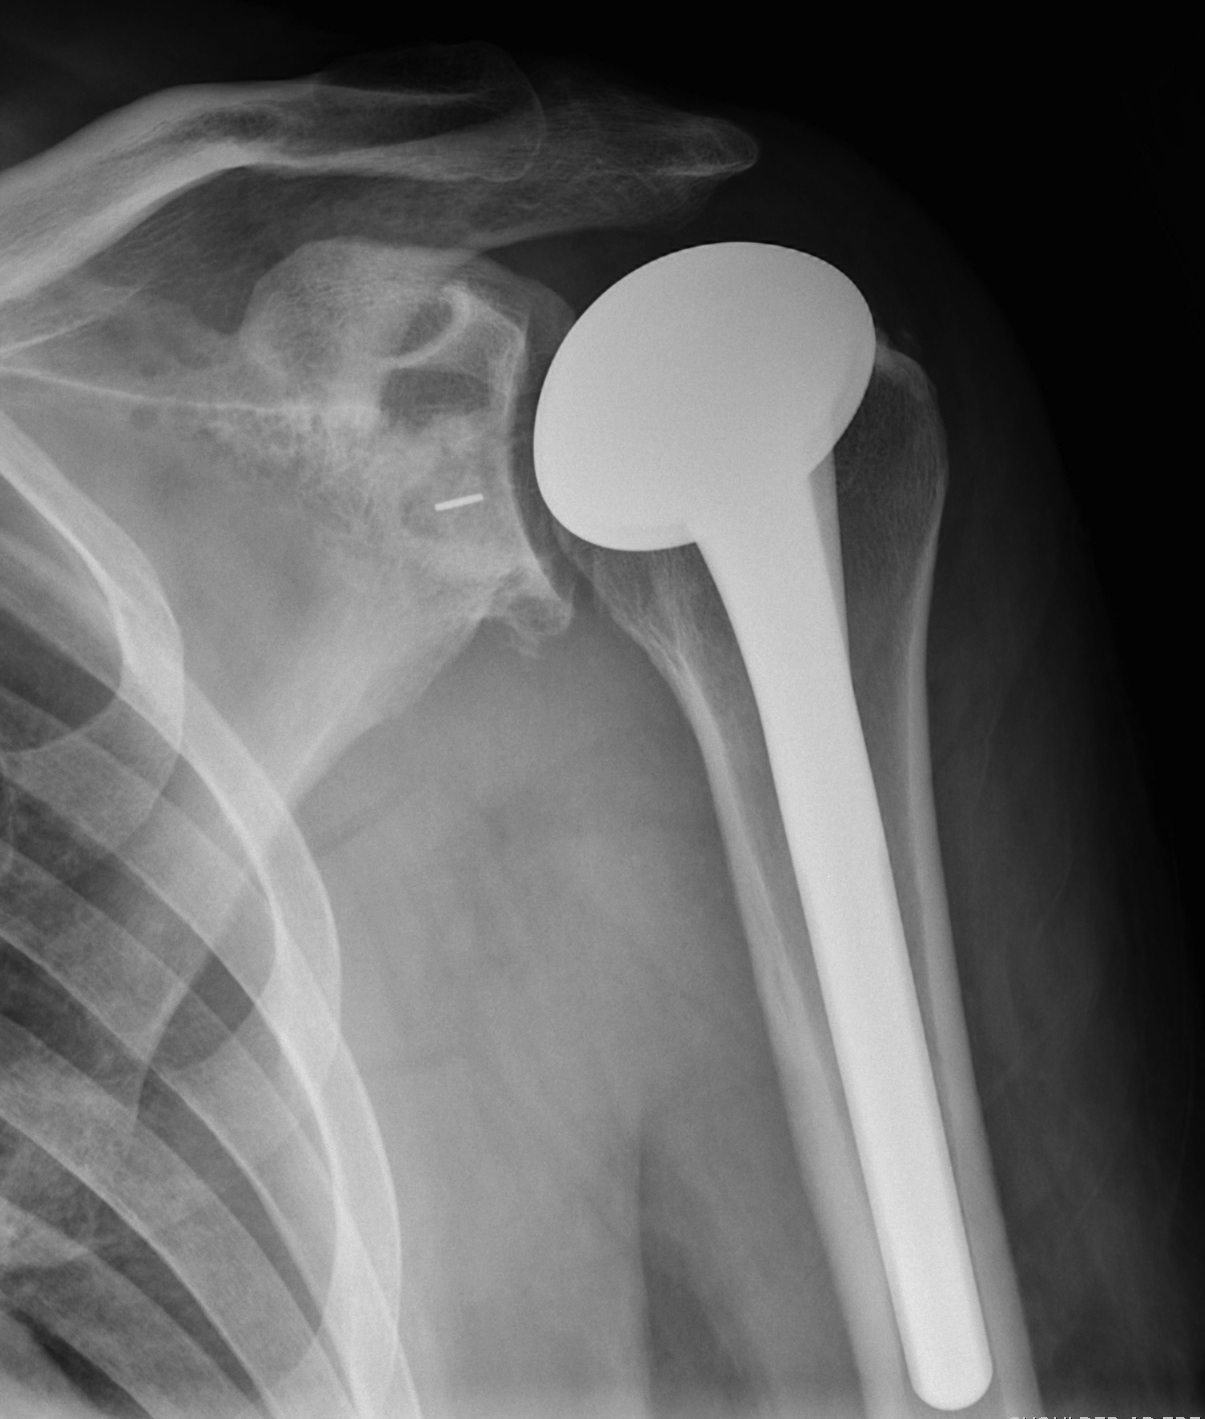

Subscapularis failure

Rotator cuff failure

Instability

Infection

Periprosthetic fracture

Aseptic loosening

Neurological injury

Parada et al. J Should Elbow Surg 2021

- 2224 aTSA complication rate 11%, revision rate 5.6%

RA

OA

AVN

Infection

Charcot

Paralysis of deltoid

Torn rotator cuff

Insufficient glenoid bone stock